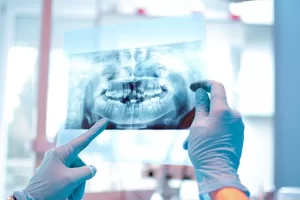

Diagnostic corect: Evaluăm fiecare caz individual pentru a găsi cea mai potrivită soluție.

Tehnologie modernă: Intervenții rapide, cu durere minimă și recuperare accelerată.